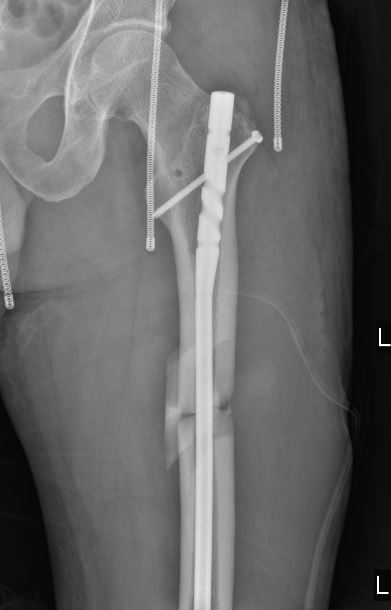

上周,我院骨科二病区张宏主任实施了西安凤城医院首例骨科机器人手术,为一名股骨干骨折的患者完成微创髓内钉内固定手术。机器人定位后,置入髓内钉一次成功,置入位置与预期位置分毫不差。

利用高科技机器人完成手术,优势是手术中的定位非常准确,可以达到毫米级,创伤可以明显缩小,除了髓腔的少量出血外,皮肤软组织的切口很小,出血也很少。而如果采用传统手术方式的话,术中出血量可达800毫升以上,非常不利于恢复。